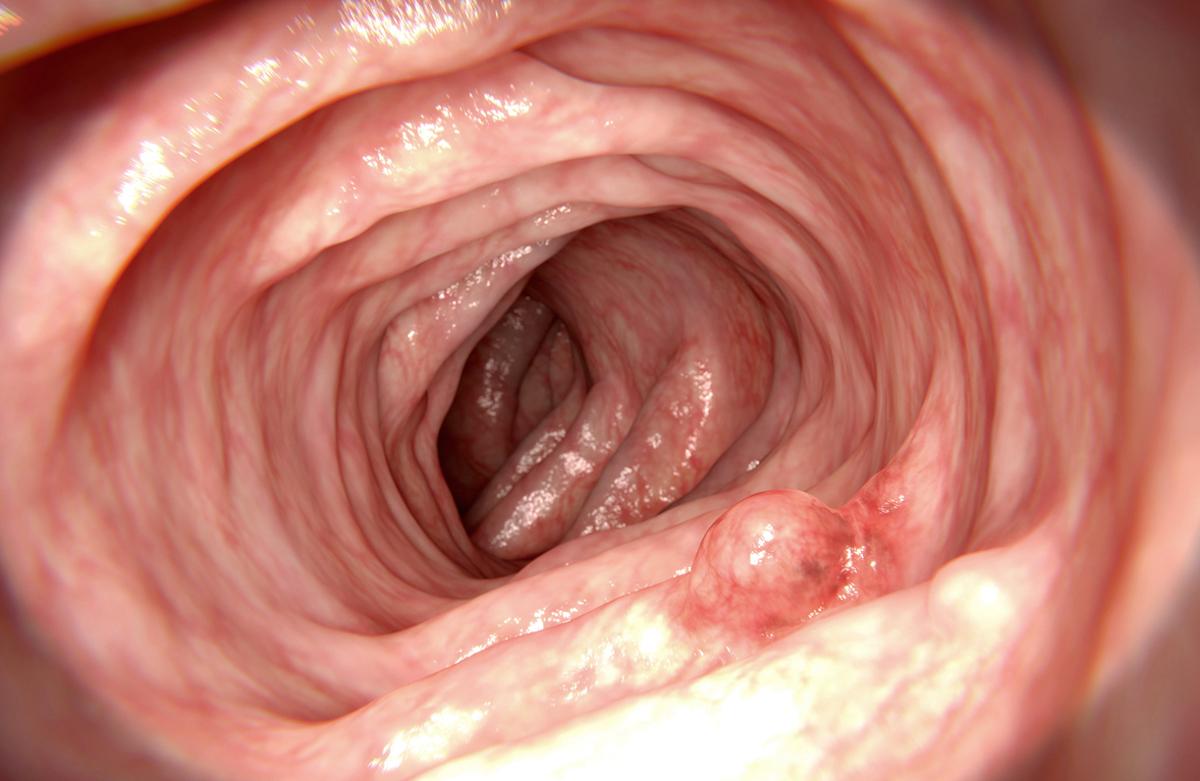

- Mohammed Haneefa Nizamudeen/istock

Les auteurs insistent également sur l’importance de continuer le dépistage standard des tumeurs du sein ou encore du cancer colorectal pendant que les tests MCED sont perfectionnés et validés pour des maladies comme le cancer du pancréas, de l’intestin grêle et de l’estomac, pour lesquelles il n’existe actuellement aucun moyen de dépistage.